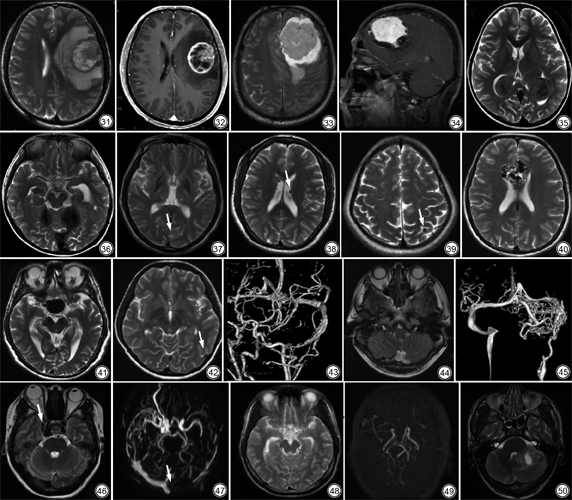

起源于第四脑室顶残留的原始神经上皮组织,肿瘤镜下排列密集,核浆比高及存在促结缔组织增生成分[20]。是最常见的儿童后颅窝恶性肿瘤。超过90%的髓母细胞瘤位于小脑,其中3/4以上发生于小脑蚓部;位于小脑半球者多见于年长儿童、青年人和成人。T1WI呈等到低信号,T2WI多为等、低或高信号,信号多不均匀,囊变常见,多为小囊变,DWI上病灶呈高信号,增强后多为不均匀强化,灶周水肿不明显(图27,28)。

脑淋巴瘤镜下细胞密度高、核浆比高、纤维组织丰富[21]。任何年龄均可发病,多见于中老年人;可发生于脑内任何部位,但常发生在中线深部脑组织或邻近脑表面,容易累及胼胝体而侵犯对侧半球。病灶多为圆形或类圆形,少数为不规则形;T1WI为等或稍低信号,T2WI为等、稍低或稍高信号,囊变坏死少见;增强扫描肿瘤组织显著强化,并持续较长时间,少数呈特征性的“握拳样”强化。MRS上可见Lip峰;由于肿瘤乏血管,因而脑血容量减低,PWI上表现为低灌注[22](图29,30)。

病灶多位于大脑半球皮质下白质区,发病率依次为颞叶、顶叶、额叶和枕叶。常浸润邻近皮质或通过胼胝体侵犯对侧大脑半球。肿瘤恶性程度高,生长速度快,常伴发出血、坏死、囊变。多数胶质母细胞瘤的肿瘤实质T2WI呈高信号,少数由于细胞密集[23],T2WI呈低信号。增强呈不规则厚壁花环样强化(图31,32)。MRI的作用在脑肿瘤中的应用已不止于明确诊断,术前预测、术中指导及术后预后评估均具有较大价值。依据2017年WHO中枢神经系统肿瘤最新分类,胶质瘤除传统病理类型的区分外,更是细化增加分子病理的类型,也给影像工作也提出了新的挑战。Patel等[24]研究发现T2-FLAIR不匹配可高度预测IDH突变1p/19q非共缺失胶质瘤分子亚型。MRI上除常规序列外,越来越多的序列包括常用的DWI、DCE、PWI、MRS、DTI以及不常用的IVIM、DKI、APT等加入到帮助诊断队伍中,这些序列术前分级及术后评估均具有一定价值,且可提供定量指标进行评估[25]。

脑膜瘤起源于蛛网膜粒细胞,多位于大脑凸面,好发于中年女性。T1WI上多为等信号,T2WI多为稍高信号,少数为等或低信号,信号多均匀一致,钙化明显者在T2WI上呈明显低信号。增强扫描多为均匀且明显强化,约半数见脑膜尾征;肿瘤内和(或)附近见流空信号,可使邻近颅骨增生、板障增厚,少数见颅骨破坏。部分脑膜瘤可出现囊性变,或沿颅内孔道蔓延[26]。位于鞍旁累及海绵窦时,包绕并压迫颈内动脉致其狭窄,此征象有助于与垂体腺瘤鉴别(图33,34)。人工智能除在胸部CT广泛应用外,目前国内外也有多数研究将其运用于脑膜瘤诊断,主要方面为脑膜瘤病理级别分级、鉴别诊断及瘤周水肿的评估[27]。

脂质肉芽肿病(Erdheim-Chester disease,ECD)和窦性组织细胞增生伴巨大淋巴结病(Rosai-Dorfman disease,RDD)是两种少见的组织细胞增生症。ECD多见于50~60岁的男性,95%的患者有长骨受累,半数患者具有颅内病灶。但多累及垂体柄和下丘脑,表现为漏斗增大、垂体柄强化而无形态学改变、下丘脑T2高信号。也可累及脑膜,表现为脑膜弥漫性增厚或肿块样强化[28, 29]。RDD最常见于儿童,男性略多见,最常见表现是非特异性无痛性淋巴结肿大(最常见于颈部),伴发热、血沉增快、轻度贫血。RDD累及颅内可表现为脑膜肿块样病灶,病灶内无出血及钙化,周围无水肿,罕见者累及脑室脉络丛[30]。ECD和RDD均可罕见地出现轴外肿块,类似脑膜瘤,T2WI呈低信号、骨受累、年龄和性别等有助于鉴别(图35,36)。

钙沉积出现于多种疾病中,包括甲状旁腺功能减退、假性甲状旁腺功能减退及假假性甲状腺旁腺功能减退、Fahr病、结节性硬化、颅颜面血管瘤病(Sturge-Weber综合征)、肿瘤钙化、慢性期感染等。前四种疾病,虽然其病因不同,但影像学表现类似,均表现为基底节钙沉积;CT上表现为苍白球、壳核和尾状核双侧对称粗大钙化,丘脑、皮层下白质和齿状核也可受累;T1WI高信号、T2WI低信号,T2*WI或SWI上可出现开花伪影[31](图37),确诊依赖于实验室检查。

结节性硬化几乎累及所有器官和系统,尤以脑、皮肤、肾脏、心脏表现突出,病理改变为错构瘤。典型临床表现为癫痫、智力低下、面部皮肤皮脂腺瘤三联征。中枢神经系统表现包括:皮层结节、脑白质异常、室管膜下结节、室管膜下巨细胞星形细胞瘤[32]。钙化性室管膜下结节T2WI呈侧脑室壁上类圆形低信号灶(图38)。

Sturge-Weber综合征主要特征为面部皮肤毛细血管畸形(葡萄酒痔)、软脑膜血管瘤病和青光眼[33]。软脑膜血管瘤多为单侧,好发于顶枕叶,伴不同程度脑萎缩,皮质可见不同程度曲线样钙化及脑回样脑膜强化;脑实质内静脉畸形;侧脑室脉络丛增大、强化。

颅内感染性病变慢性期出现钙盐沉积,常见于脑囊虫病吸收钙化期,T2WI呈小圆形低信号,无水肿、占位效应,无强化(图39)。

颅内多种肿瘤内可伴发钙化,包括少突胶质细胞肿瘤、节细胞胶质瘤、颅咽管瘤、脑膜瘤等。少突胶质细胞肿瘤多位于大脑皮层,可见条带状钙化,增强后无强化或轻度强化,间变者可强化明显。节细胞胶质瘤多表现为囊实性肿块,多有钙化,实性部分可见明显强化,占位效应和灶周水肿轻。颅咽管瘤多位于鞍上或鞍内鞍上,囊性或囊实性,少数可为实性,T1WI信号多变,T2WI呈高信号;囊壁和实性部分可钙化,T2WI呈弧形或片状低信号;增强后实性部分和囊壁强化。

铁在脑组织中异常代谢与沉积会引起神经细胞的损伤及死亡。帕金森病患者铁首先沉积于黑质,且随着病变进展,逐步向基底节区迁延[34]。

甲苯是工业溶剂的最重要成分,见于胶水、油漆稀释剂、墨水等,可被中枢神经系统快速吸收。长期接触甲苯可导致严重的不可逆性认知损害,在青少年和年轻的成人,这是诊断甲苯中毒的重要线索。MRI表现为广泛脑室周围白质病变,在T2WI和FLAIR上表现为高信号。以及丘脑、基底节和黑质的显著T2低信号,原因不明,可能与铁沉积有关;伴有全脑萎缩及脑室扩张和胼胝体变薄[31]。

肝豆状核变性是由铜代谢的异常所引起,可累及全身多个脏器系统,比较典型的表现是角膜K-F环、颅内基底节受累和肝硬化。最常累及豆状核,其次是脑干、尾状核、丘脑,少部分患者累及大脑皮层,部分患者出现脑萎缩。多表现为T1WI低信号T2WI高信号,少部分T2WI低信号,T2WI低信号可能是由于铜离子的过量沉积而带来的顺磁性效应所造成[35]。

血管性病变和肿瘤内异常的血管由于流空效应在T2WI上呈明显低信号。动静脉畸形位于脑实质内,由供血动脉、畸形血管团及引流静脉所组成(图40)。动脉瘤表现为与载瘤动脉相通的流空信号,较大者血流慢的部分T2WI为高信号,若瘤腔内存在血栓,多表现为混杂信号(图41)。软脑膜动静脉瘘为扩张的软脑膜动脉和静脉直接沟通,瘘口位于脑表面,脑表面的皮层静脉明显扩张,甚至可形成静脉湖(图42,43)。硬脑膜动静脉瘘为正常供应脑膜、颅骨、肌肉等的动脉与静脉窦壁内小静脉直接沟通,多发生于后颅窝,当存在皮层静脉反流时可见较多的扩张的皮层静脉(图44,45)。颈动脉海绵窦瘘是连接颈动脉与海绵窦的异常血管分流,血流可直接来源于颈内动脉海绵窦段,也可间接来源于颈内动脉或颈外动脉的硬脑膜分支[36](图46,47)。烟雾病是指一侧或双侧颈内动脉虹吸部及大脑前、中动脉起始部严重狭窄或闭塞,颅底软脑膜、穿通动脉等小血管代偿增生形成脑底异常血管网,T2WI上颈内动脉和(或)大脑中动脉流空消失,鞍上池内见多个细小紊乱的侧支血管,增强后广泛皮层血管强化呈“常春藤征”[37](图48,49)。胶质母细胞瘤、脑膜瘤、血管母细胞瘤、孤立性纤维瘤/血管外皮瘤及中枢神经细胞瘤内可见流空血管,这也成为这些肿瘤的重要鉴别点(图50)。